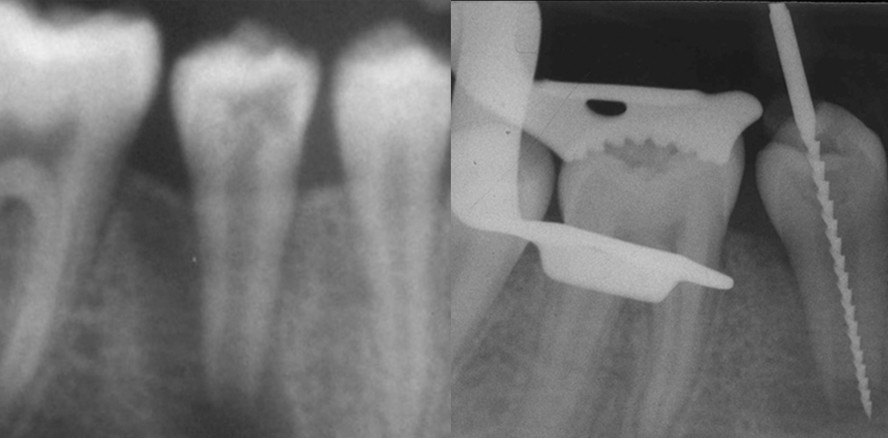

Abb. 1a: 45 apikale Osteolyse (Endo-Paro-Läsion) bei nicht abgeschlossenem Wurzelwachstum (Ausschnitt aus Orthopantomogramm).

Abb. 1b: Röntgenmessaufnahme an Zahn 45.

Abb. 1c: Wurzelkanalfüllung mit Guttapercha und AH 26 nach Kalziumhydroxideinlagen (Wechsel alle fünf bis sechs Wochen für zwölf Monate wegen Blutung bei offenem Apex); man erkennt die weitere Verlängerung der Wurzel sowie die erfolgte Apexifkation.

Abb. 1d: Kontrollaufnahme vier Jahre nach Wurzelkanalfüllung.